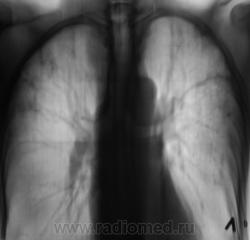

Вот такой случай. Пациент на учете по поводу фиброзно-кавернозного туберкулёза.

Сомнения вызвала тень, помеченная желтой стрелкой. На наш взгляд, это был растущий гриб. Однако возобладало мнение, что "это" участок некроза, так как не было "симптома погремушки"

Однако, в последующем, лабораторно наличие "гриба" было доказано.

И, уже через год, при плановом обследовании данного пациента, мы "поимели" такие картинки.